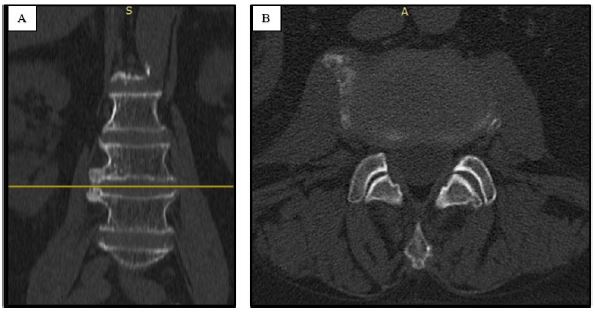

A 72-year-old male patient presented to our institution with a history of right crural neuralgia that had begun a few months prior. At the neurological examination there was no evidence of sensory or motor deficits in the lower limbs, but she experienced significant walking impairment due to intense pain. A spinal lumbar Magnetic Resonance Imaging, MRI, (Figure 1A) revealed the presence of a right lumbar osteophyte at the zygapophyseal joint between the third and fourth lumbar vertebra, resulting in impingement of the ipsilateral psoas muscle. A lumbar CT scan was not performed before the surgery.

Figure 1: Lumbar MRI displaying the right osteophyte the third and fourth lumbar vertebra: coronal (A) and axial planes (B).